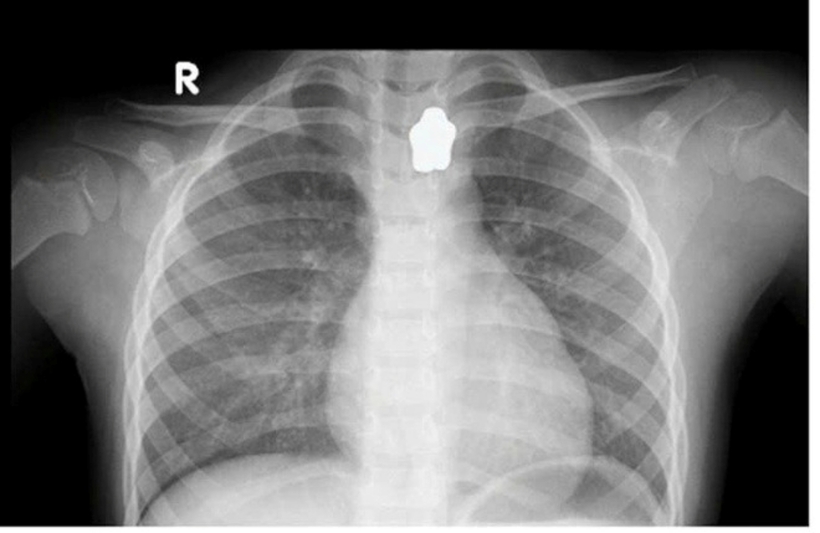

Cụ thể, bệnh nhi N.N.N.Y (5 tuổi, ngụ TP.Thủ Đức, TPHCM) nuốt phải nam châm hình ngôi sao trong lúc ăn cơm. Bệnh nhi nhập viện trong tình trạng mắc nghẹn, đau vùng cổ, khó thở nhẹ. Kết quả chụp X-quang ghi nhận, dị vật hình ngôi sao cản quang mắc tại vùng cổ.

Kết quả chụp X-quang ghi nhận, dị vật hình ngôi sao cản quang mắc tại vùng cổ. Ảnh: Sức Khỏe & Đời Sống